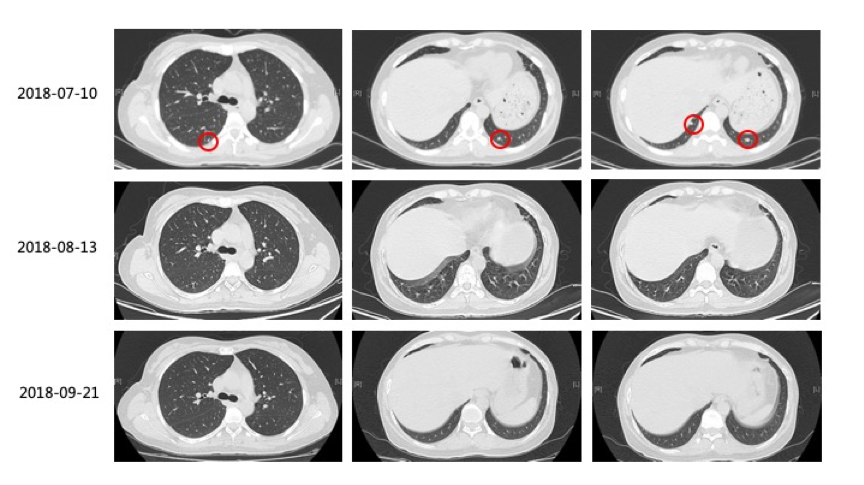

2)2018-8-13复查CT:双肺病灶缩小,脾脏出现多发新病灶。建议继续口服维莫非尼治疗1个月后复查。

3)2018-09-21复查CT:原双肺内多发转移瘤,较前眀显缩小、减少,大部分已未见眀确显示。脾内病灶较前明显缩小、减少。疗效PR,建议联合免疫治疗。

(图1:维莫非尼治疗3周期后,原双肺内多发转移瘤较前眀显缩小、减少,脾内病灶较前明显缩小、减少;疗效评估为PR)